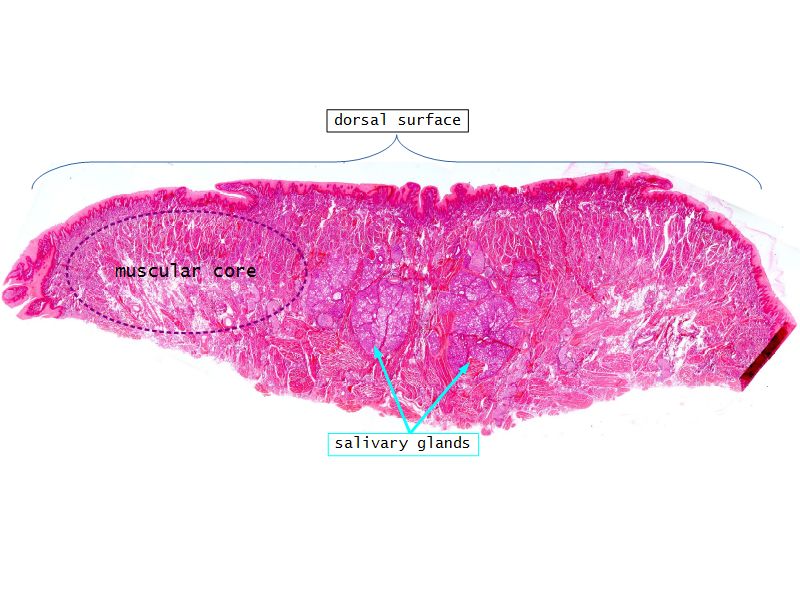

Absorption - Alimentary tract